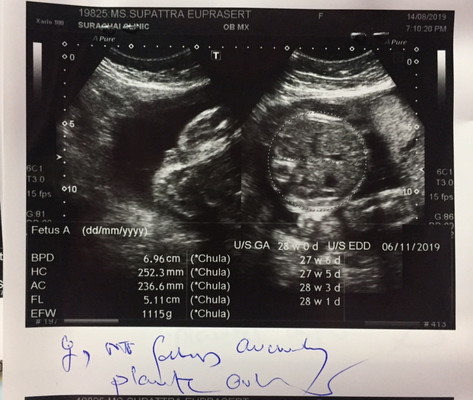

รูปภาพแบบนี้ ช หรือ ญ คร่

ตอนซาวหมอบอกว่าเพศ ญ แต่อื่นบอกแต่ว่า ได้ลูกชายคร่ ตอนนี้ 33+6 แล้วคร่

ไม่เห็นภาพส่วนหว่างขา ดูไม่ออกจ้า